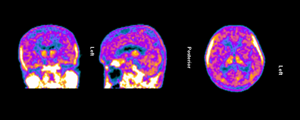

The clinical trial launch is supported by new TSPO-PET imaging evidence demonstrating persistent and widespread microglial activation in an Alzheimer’s patient despite treatment with lecanemab, confirming that neuroinflammation remains present even after amyloid plaque reduction. Lecanemab, marketed by Eisai and Biogen as Leqembi®, is one of the two FDA-approved anti-amyloid therapies for treating early Alzheimer’s and is proven to reduce beta-amyloid plaques.

Figure 1. TSPO-PET scan of an Alzheimer’s patient treated with lecanemab demonstrating persistent and widespread microglial activation throughout the brain.

Dr. Howard Weiner, Chairman of Tiziana’s Scientific Advisory Board and co-director of the Ann Romney Center for Neurologic Diseases at Brigham and Women’s Hospital, a founding member of Mass General Brigham, stated, “This PET finding is a critical insight: clearing amyloid does not turn off the brain’s inflammatory response. We believe intranasal foralumab directly addresses this residual neuroinflammation by inducing regulatory T cells to migrate to the brain and calm activated microglia — a mechanism we have already shown reduces microglial activation in secondary progressive multiple sclerosis.”

Figure 1

TSPO-PET scan of an Alzheimer’s patient treated with lecanemab demonstrating persistent and widespread microglial activation throughout the brain.